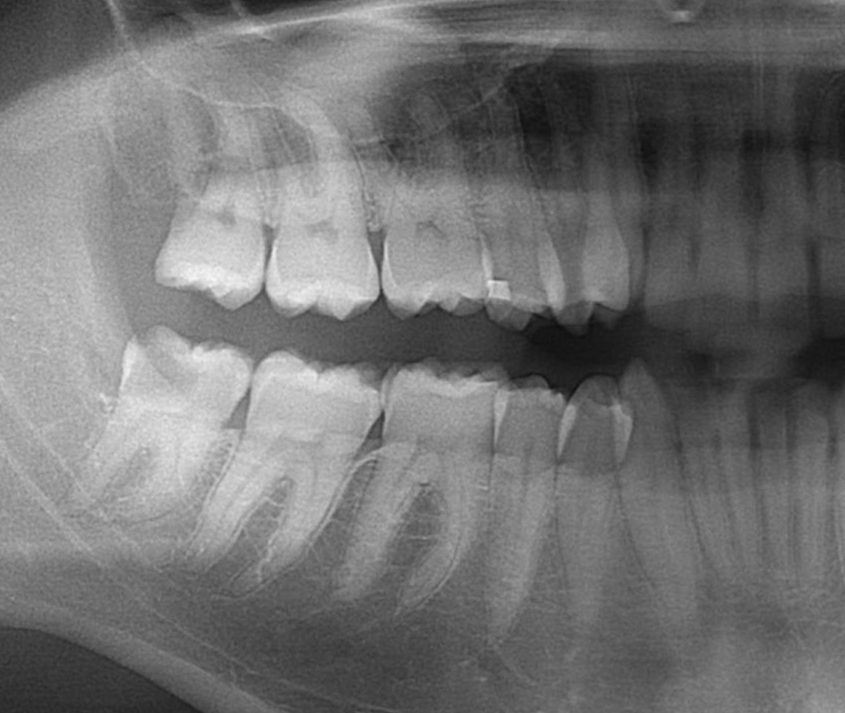

Wisdom Tooth with a cavity

Our patient was having pain due to a deep cavity in the lower wisdom tooth.  His wisdom teeth were too far back for him to brush affectively.  Both the upper and lower wisdom teeth were extracted painlessly.